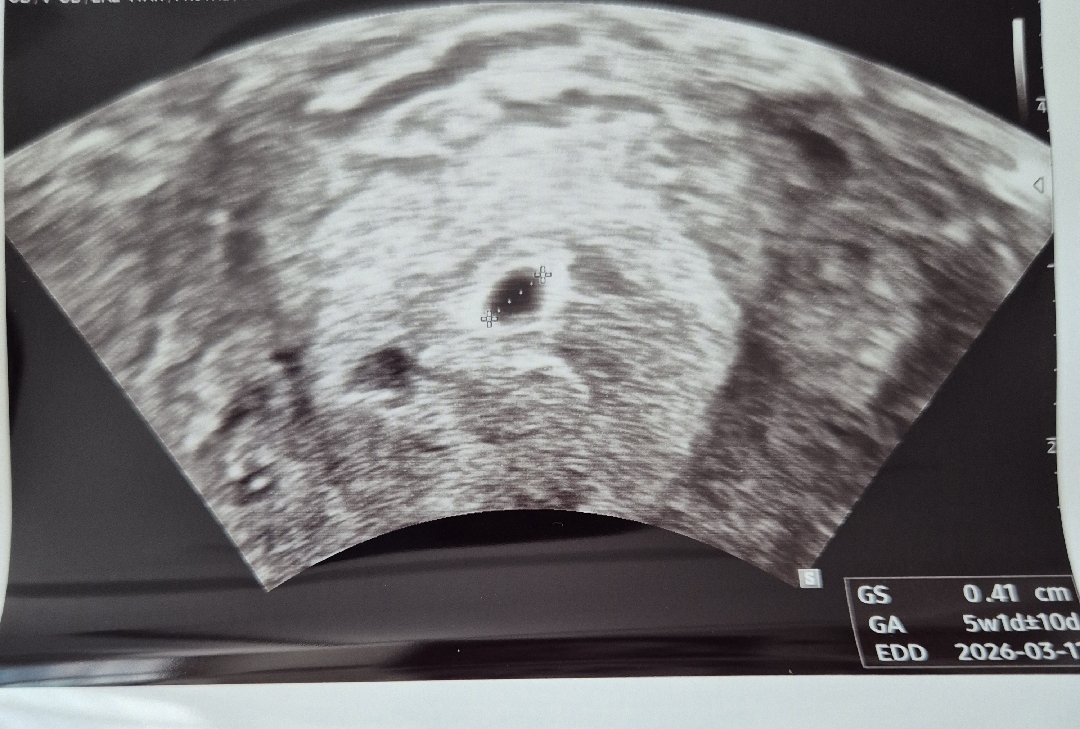

4주 4일차! 아기집 보고 왔어요

작년 12월 양수과소증으로 유산 후 아기가 다시 찾아왔네요! 막생은 6월10일이고 시기상으로는 4주 4일 정도 된다고 하는데 초음파 종이에는 5w 1d 라고 되어있네요? 아기집이 조금 커서 날짜가 차이나는거겠죠? 병원에서 물어보면 되는데 넘 좋아서 넘 좋아서 물어보는걸 까먹었어요ㅠ